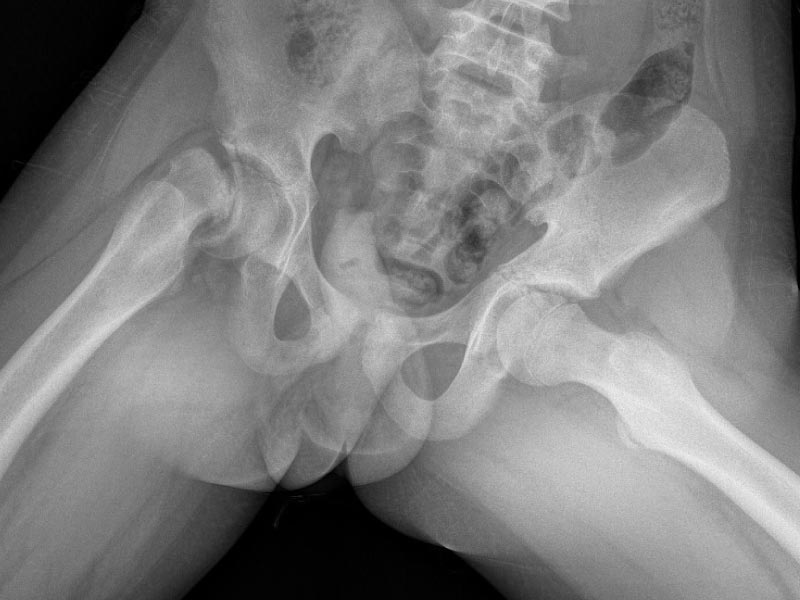

Caso No. 3 - Displasia de cadera derecha con luxación

Preoperación

Posoperación

Displasia de cadera

Diagnóstico: Displasia de cadera derecha con luxación

Tratamiento quirúrgico realizado: reducción abierta, acetabuloplastía y acortamiento femoral

Operada a los 5 años por no diagnosticarse antes, ahora tiene una cadera derecha útil